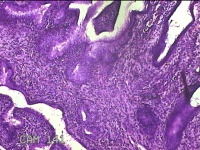

宫颈6点外缘、9点组织

性别

女

年龄

18岁

临床诊断

宫颈炎性疾病

一般病史

宫颈高危HPV感染

标本名称

大体所见

1.“宫颈6点外缘组织”:灰白粉红色不规则组织0.7x0.5x0.3cm两块。 2.“宫颈9点组织”:灰白粉红色不规则组织0.5x0.3x0.2cm一块。

良性病变。